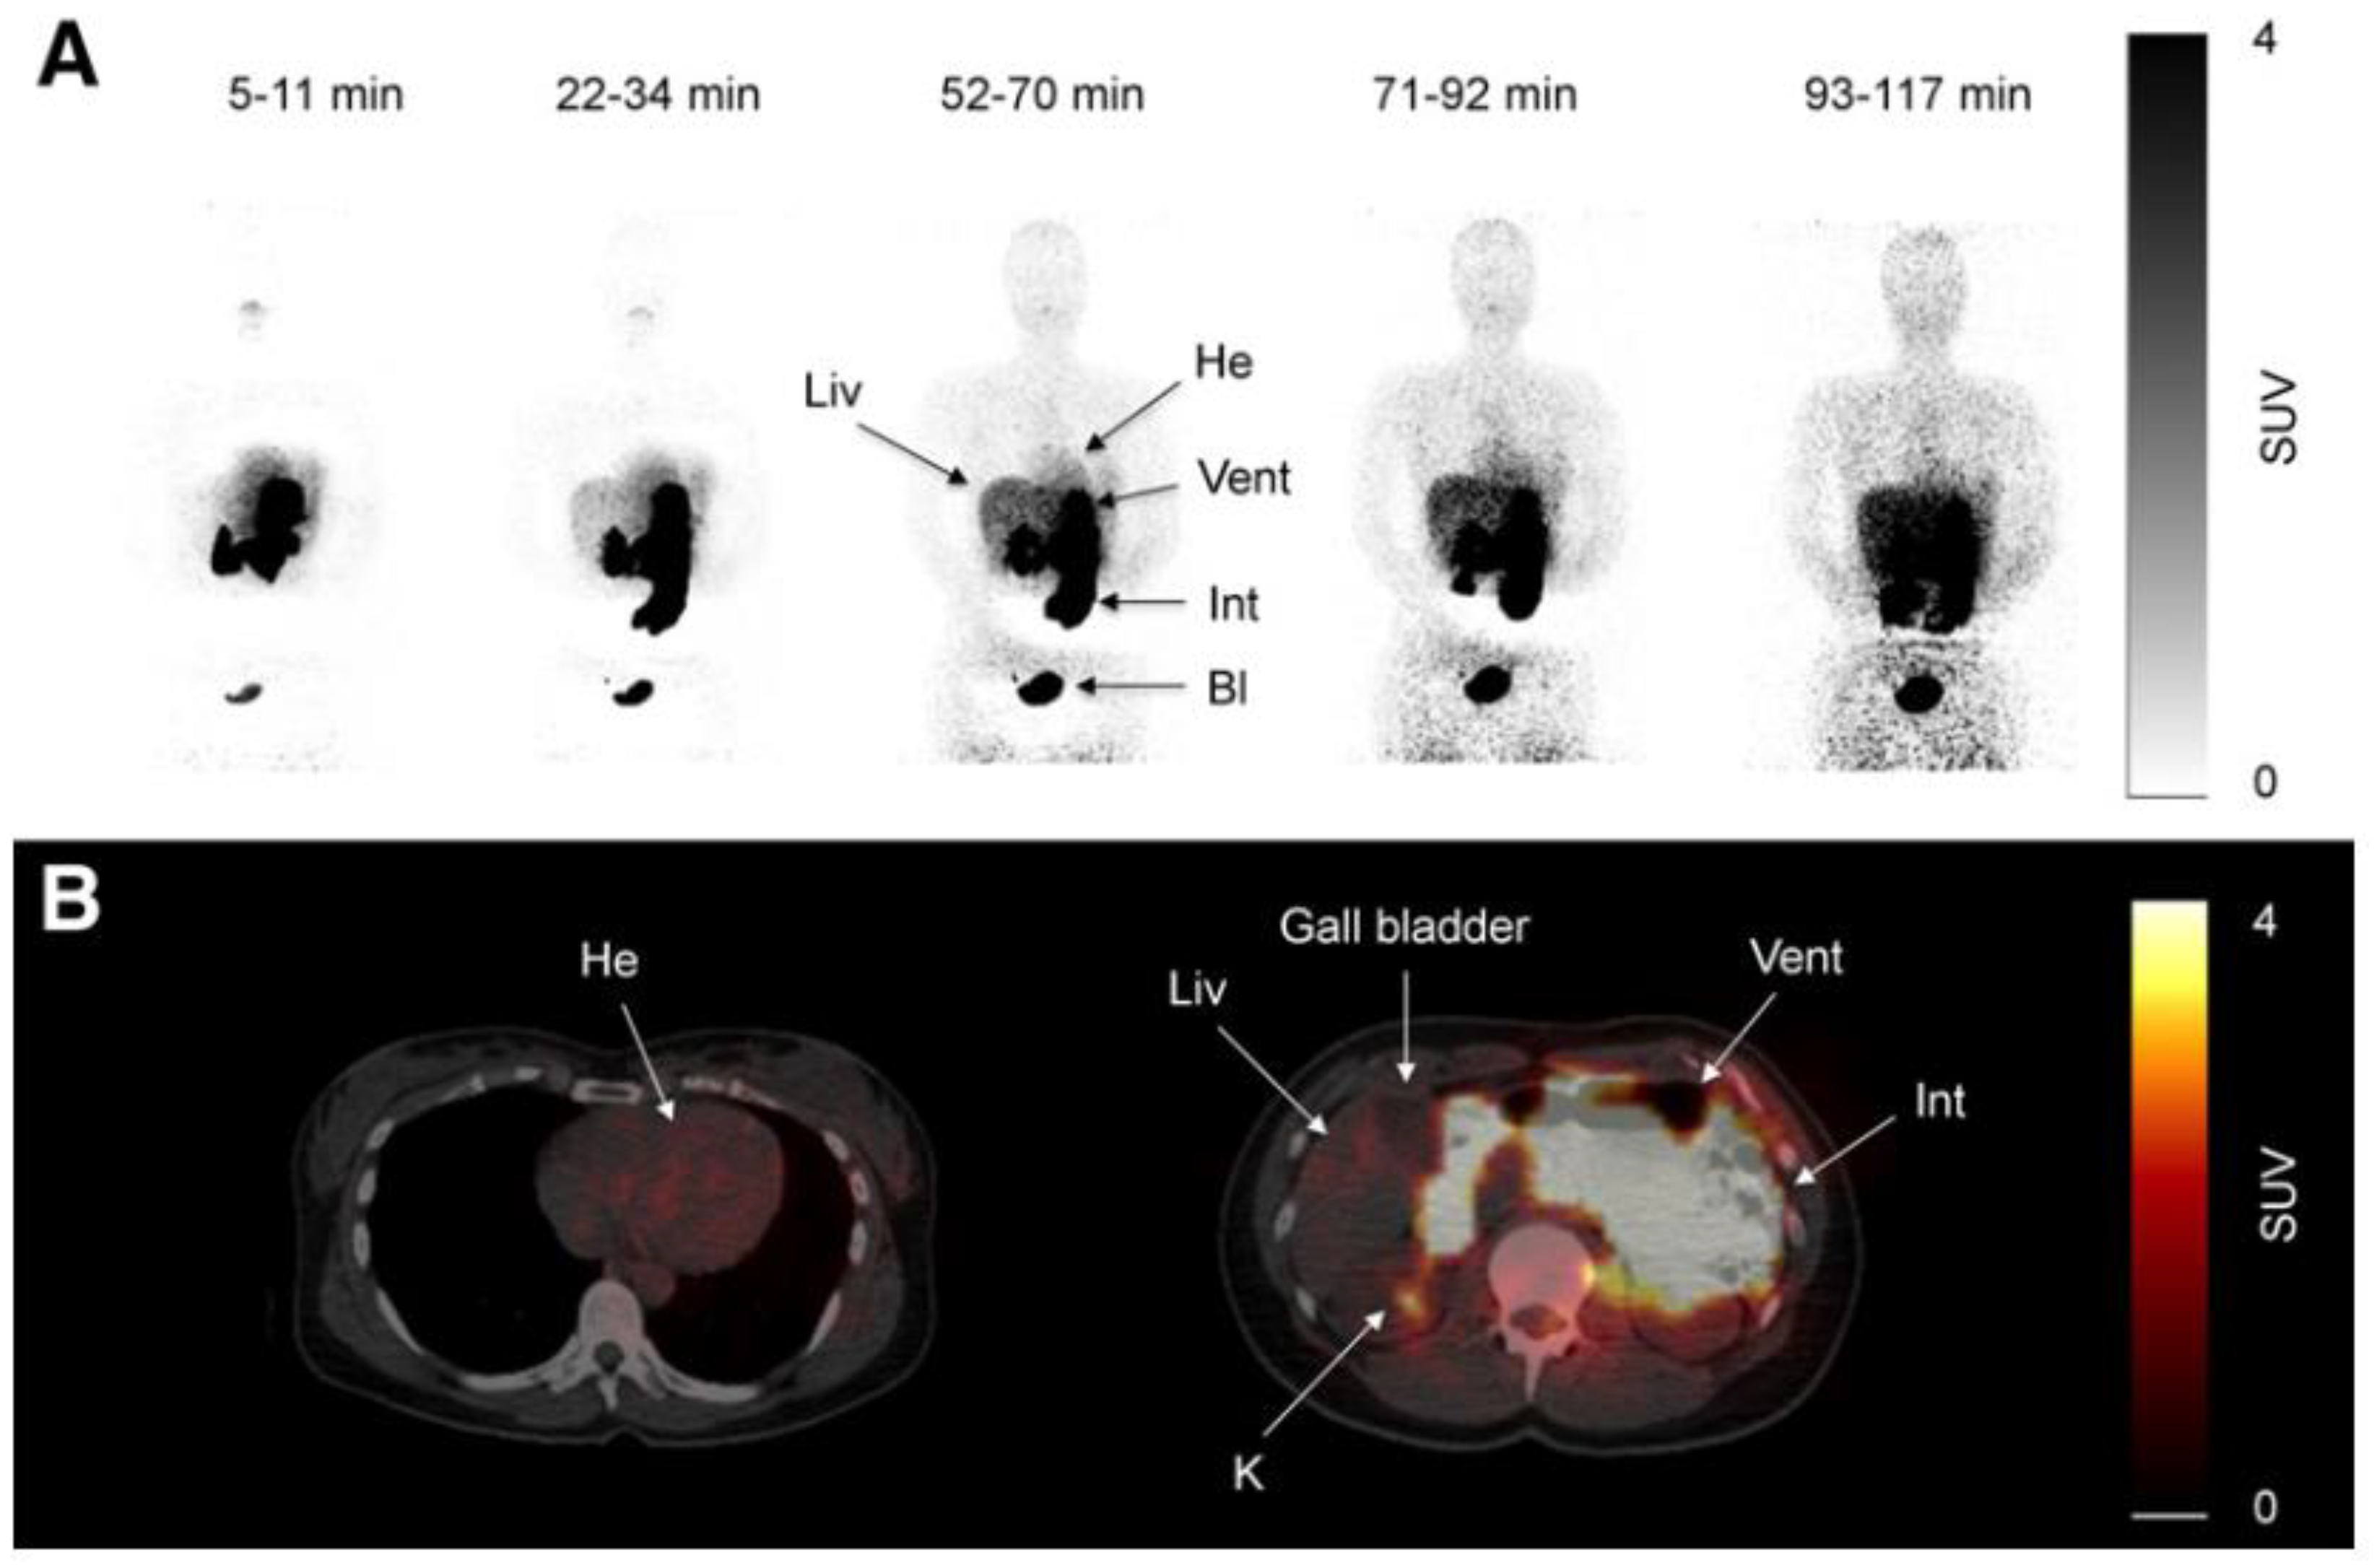

- Gormensen LC, Sundelin EI, Jensen JB, Vendelbo MH, Jakobsen S, Munk OL, Christensen MMH, Broesen K, Froekiaer J, Jessen N.In vivo Imaging of Human C11-Metformin in Peripheral Organs:Dosimetry, Biodistribution, and Kinetic Analyses.J Nucl Med 2016;57(12):1920-1926.

- 179..Kim S, Chung JK, Kim BT, Relationship between gastrointestinal F-18-fluorodoxyglucose accumulation and gastrointestinal symptoms in whole-body PET.Clin Positron Imaging 1999;2:273-279.

- Gontier E, Fourme E, Wartski M, Blondet C Bonardel G, Le Stanc E, Mantzarides M, Foehrenbach H, Pecking A-P, Alberini J-L.High and typical F18-FDG bowel uptake in patients treated with metformin.Eur J Med Mol Imaging 2008;35:95-99.

- Morita Y, Nogami M, Sakaguchi K, Okada Y, Hirota Y, Sugawara K, Tamori Y, Zeng F, Murokami T, Ogawa W.:Enhanced Release of Glucose Into Intraluminal Space of the Intestine Associated With Metformin Treatment as Revealed by [18F]Fluorodeoxyglucose PET-MRI.Diabetes Care 2020;43:1796-1802. [CrossRef]

- Özülkur T, Özülkur F, Mert M, Özpacaci T.Clearance of high intestinal F18-FDG uptake associated with metformin after stopping the drug.Eur J Nucl Med Mol Imaging 2010;37:1011-1017.

- Schreuder N, Klarenbeek H, Vendel BN, Jager PL, Kosterink JGW, van Puijenbroek EP.Discontinuation of metformin to prevent metformin-induced high colonic FDG uptake:is 48 h sufficient?.Annals of Neclear Medicine 2020;34:833-839.

- Massollo M, Marini C, Brignone M, Emionite B, Salani BRiondato M, Capitano S, Fitz F, Democrito A, Amaro A, Morbelli S, Piana MMaggi D, Cilli MPfeffer U, Sambuceti G.Metformin Temporal and Localized Effects on Gut Glucose Metabolism Assessed Using F18-DG PET in Mice.J Nucl Med 2013;54:259-266.